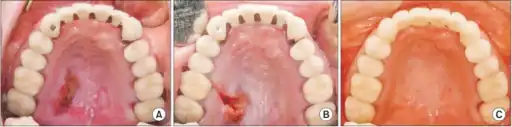

Necrotizing sialometaplasia (NS) is a benign, ulcerative lesion, usually located towards the back of the hard palate. It is thought to be caused by ischemic necrosis (death of tissue due to lack of blood supply) of minor salivary glands in response to trauma. Often painless, the condition is self-limiting and should heal in 6–10 weeks.

Initially, the lesion is a tender, erythematous (red) swelling. Later, in the ulcerated stage, the overlying mucosa breaks down to leave a deep, well-circumscribed ulcer which is yellow-gray in color and has a lobular base.[1]